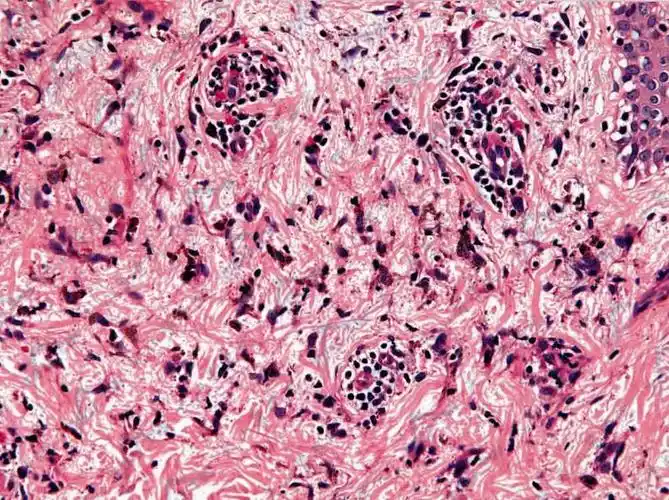

颈部假性皮萎缩组织病理